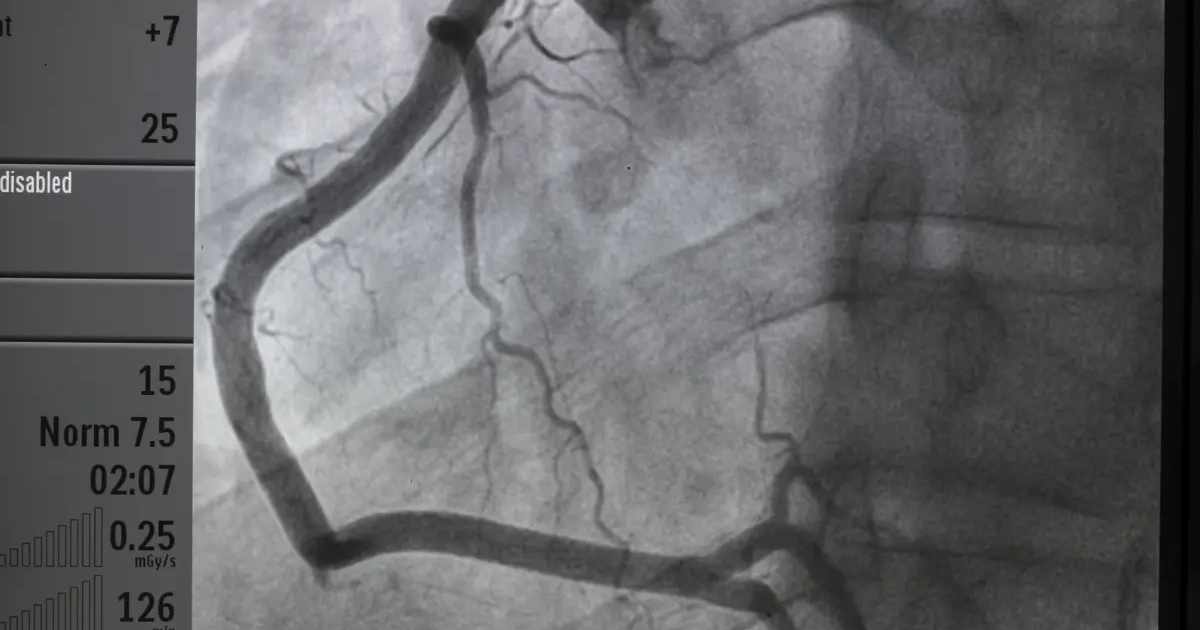

Koronarografia, znana również jako angiografia wieńcowa, to inwazyjne badanie diagnostyczne służące do oceny stanu naczyń wieńcowych – tętnic dostarczających krew do serca. Dzięki temu badaniu lekarze mogą zidentyfikować zwężenia, blokady lub inne nieprawidłowości w przepływie krwi. Badanie to jest niezwykle pomocne w diagnozowaniu choroby niedokrwiennej serca, zawału mięśnia sercowego czy innych schorzeń układu krążenia.

Przez małe nacięcie lekarz wprowadza cienki cewnik do tętnicy, najczęściej w nadgarstku (tętnica promieniowa) lub w pachwinie (tętnica udowa). Cewnik jest prowadzony aż do naczyń wieńcowych pod kontrolą fluoroskopii (RTG w czasie rzeczywistym).Podanie kontrastu

Do naczyń wieńcowych wstrzykiwany jest środek kontrastowy, który pozwala na dokładne uwidocznienie tętnic na obrazie RTG. Dzięki temu lekarz może ocenić ich przepływ i zidentyfikować ewentualne zwężenia lub blokady.Analiza wyników

Po wykonaniu zdjęć RTG lekarz ocenia stan naczyń wieńcowych. Jeśli zostaną wykryte zwężenia, w niektórych przypadkach możliwe jest natychmiastowe wykonanie angioplastyki, czyli poszerzenia naczynia za pomocą balonika lub wszczepienia stentu.